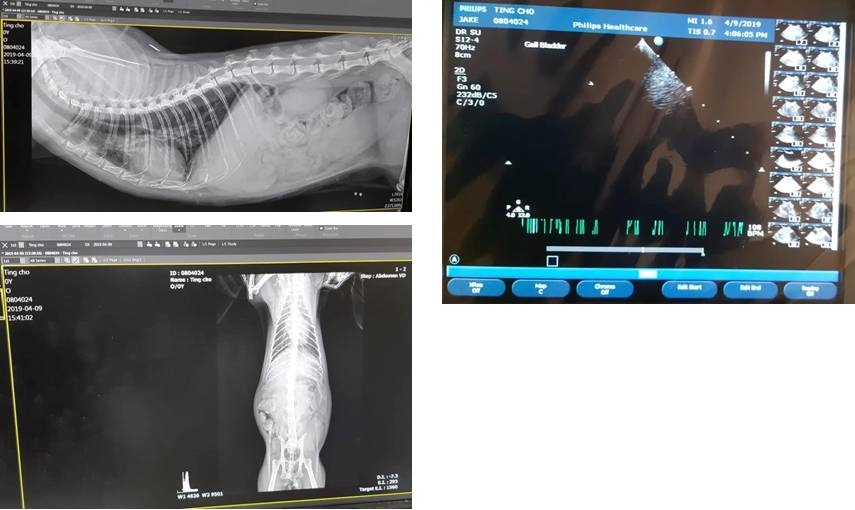

4月9日定定突然沒有吃罐罐、還嘔吐了,協會立即為她約診,經過血檢、超音波、X光檢查,定著有胰臟炎,脾臟也較為腫大因此留院以靜脈注射治療,至4月11日狀況穩定、恢復食慾,即辦理出院,醫師囑附仍須回診追蹤檢查。

4/9 定著 沐恩初診 林文傑醫師

體重:3.995kg

體溫:38.0

定著因食慾明顯變差、有吐,今日臨時約診沐恩檢查,住院。

1. 血檢結果:有胰臟炎,發炎蛋白、腎指數偏高,紅血球指數偏低,白血球2萬3。

2. 超音波檢查:脾臟較大一些、腸道淋巴結腫。

3. 觸診:左下腹摸到一處鼓起疑似疝氣,乳腺摸起來有點異樣。

林院長說明: 先朝胰臟炎的方向治療,待胰臟炎問題解決後再進行一次檢查,因須注射靜脈輸液,因此定著今日住院治療。